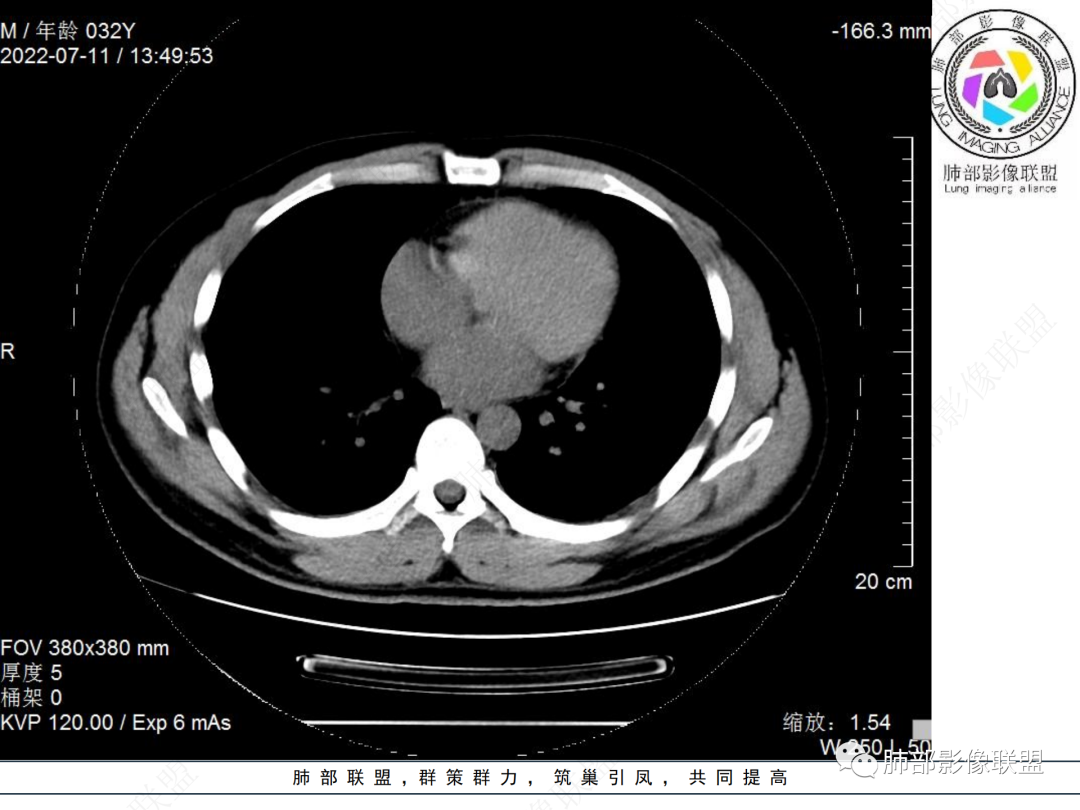

左肺下叶后基底段开口处腔内见壁结节,花生米样,宽基底,补充增强及矢状位重建,确定我无向壁外突破浸润生长,另见强化的特点,临床触之易出血,类Ca可能性大。

年轻男性,咳血,左肺下叶后基底段支气管腔内结节,边缘光滑,首先考虑青年三件套,类癌大于粘液表皮样癌,支气管镜质软,触之易出血,鉴别血管瘤,平滑肌瘤

左肺下叶后基底段开口部结节,密度较均匀一致,边缘较光整,目测密度偏低,支气管镜示:质软、触之易出血,考虑恶性,类癌。

IMT常表现为边缘清晰的周围型结节或肿块,一般体积相对较大。大约10%-20%发生于支气管及气管腔内,表现为中央型病变,一般为单发。IMT胸部CT显示90%为单发结节或肿块。

IMT的影像表现缺乏特异性。部分肿块表现为桃尖征和边缘平直征,界限可清晰有分叶状轮廓,也可界限模糊具有粗长毛刺。肺IMT的CT表现特征与病理具有相关性,可伴有囊变、局灶性钙化、肺实变和空洞样表现。CT增强扫描呈多样性,强化形态和CT值增加幅度呈多样性。粘液血管型增强CT实性成分呈明显花环样强化,静脉期强化进一步增高,此与毛细血管增生与血管管壁通透性增加有关。囊性低密度无强化区镜下为黏液样变形、炎性渗出或坏死。梭形细胞密集型增强扫描呈渐进性延迟强化特点,但强化程度弱于黏液血管型。少细胞纤维型增强扫描实性成分强化不明显或呈轻中度强化。PET/CT上IMT具有很高的SUV值。IMT高摄取的可能原因可能与激烈炎症导致的代谢活动增加有关,这使得IMT与其他恶性肿瘤难以区分。

多发生主、叶及段支气管,支气管腔内/外生长的结节或肿块,多靠近气道分叉处。常合并神经内分泌症状。30%可伴有钙化,多点状或弥漫性钙化。增强后明显强化。